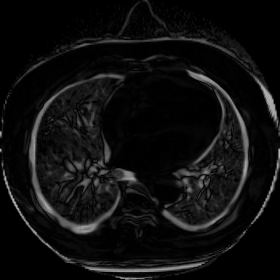

We now consider applying the proposed image registration method on real lung CT images retrieved from the National Lung Screening Trial (NLST) dataset [1]. Fig. 9(a) and Fig. 9(b) show two slices of lung CT images that we use as the source and the target (see Fig. 9(c) for the absolute intensity difference). We remark that the CT images are originally with different intensity, and so we apply an intensity histogram matching before running the registration experiment. Fig. 9(d) shows the registration result obtained by our proposed method. It can be observed that our method successfully produces a large deformation on the right lung of the source image to match that of the target image (see also Fig. 9(e) for the final absolute intensity difference). On the contrary, DDemons [47] (Fig. 9(f)), LDDMM [5] (Fig. 9(g)), Elastix [29] (Fig. 9(h)) and DROP [18] (Fig. 9(i)) all fail to produce an accurate and bijective registration result. This shows that our method is more capable of handling large deformation image registration.

We then test our method on slices of chest CT images obtained from the Open Access Biomedical Image Search Engine [2]. Fig. 10(a) and 10(b) show the source image and target image respectively, and the intensity difference is shown in Fig. 10(c). The registration result obtained by our proposed method is shown in Fig. 10(d) (see also the result with the deformed underlying grid in Fig. 10(e)). From the final intensity difference plot in Fig. 10(f), it is easily to see that our method matches not only the two large components but also the small dot at the center very well. On the contrary, DDemons [47] produces a suboptimal registration result with a significantly larger mismatch of the small component at the center (see Fig. 10(g) and Fig. 10(h)).